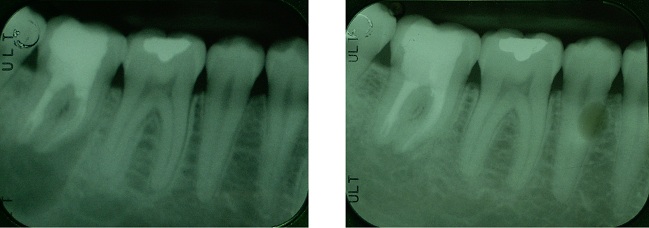

RADIOGRAFIE BITE WING

Le radiografie Bite Wing sono delle normali radiografie endorali che l'odontoiatra utilizza con una speciale tecnica di posizionamento orale in modo da ottenere, con solo due radiogrammi, un quadro diagnostico di primo livello molto esaustivo delle condizioni del paziente e delle patologie in atto nei settori posteriori.

Il grosso vantaggio per il paziente è quello di limitare il tempo di esposizione e la dose, comunque bassissima, di radiazioni assorbita.

Le dosi di radiazioni che si ricevono durante una radiografia endorale, sono normalmente molto basse. Si calcola che la dose annua tollerata per persone che vengono esposte alle radiazioni per ragioni professionali, sia equivalente a quella di circa 8.000 radiografie endorali annue.

Da questo esame si possono trarre numerose informazioni:

- Stato delle corone dentali

- Stato dei restauri conservativi (otturazioni) (2)

- Stato dell'osso

- Presenza di tasche ossee

- Presenza di impianti

- Lesioni cariose primarie (4)

- Lesioni cariose secondarie (3)

- Spicole di pericolosissimo tartaro sottogengivale (1)

- Restauri protesici con margini incongrui (5)